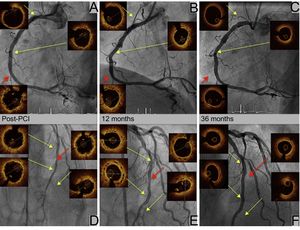

We present the case of a 36-year-old woman with familial dyslipidemia, a positive ischemia induction test and multivessel coronary artery disease, chronic occlusion of the right coronary artery and left anterior descending artery, with lesions in the diagonal branch and circumflex artery (Figure 1A-C, yellow arrows). The patient was entered in the ABSORB-CTO study and underwent complete percutaneous coronary intervention (PCI) with 8 bioresorbable vascular scaffolds (BVS): 4 in the right coronary artery (Figure 1D and Figure 2A), 2 in the left anterior descending artery (Figure 1E and Figure 2D), 1 in the diagonal branch and 1 in the circumflex artery (Figure 1F). Optical coherence tomography was also performed after the procedure and at 12 and 36 months. Dual antiplatelet therapy was continued for 3 years. At 12 months, the struts of the right coronary artery and left anterior descending artery were endothelialized (Figure 2B and E, yellow arrows), well apposed, and had more intimal hyperplasia in the overlap area (Figure 2B and E, red arrows). At 36 months, all segments remained free from restenosis (Figure 1G-I) and optical coherence tomography showed resorption of the struts (Figure 2C and F, yellow arrows), with dissolved black boxes, including the area of overlap (Figure 2C and F, red arrows).

This case of a young woman with multivessel coronary disease and complete percutaneous revascularization with 8 BVS (194mm scaffold) shows the excellent long-term outcome with resorption of the scaffolds.